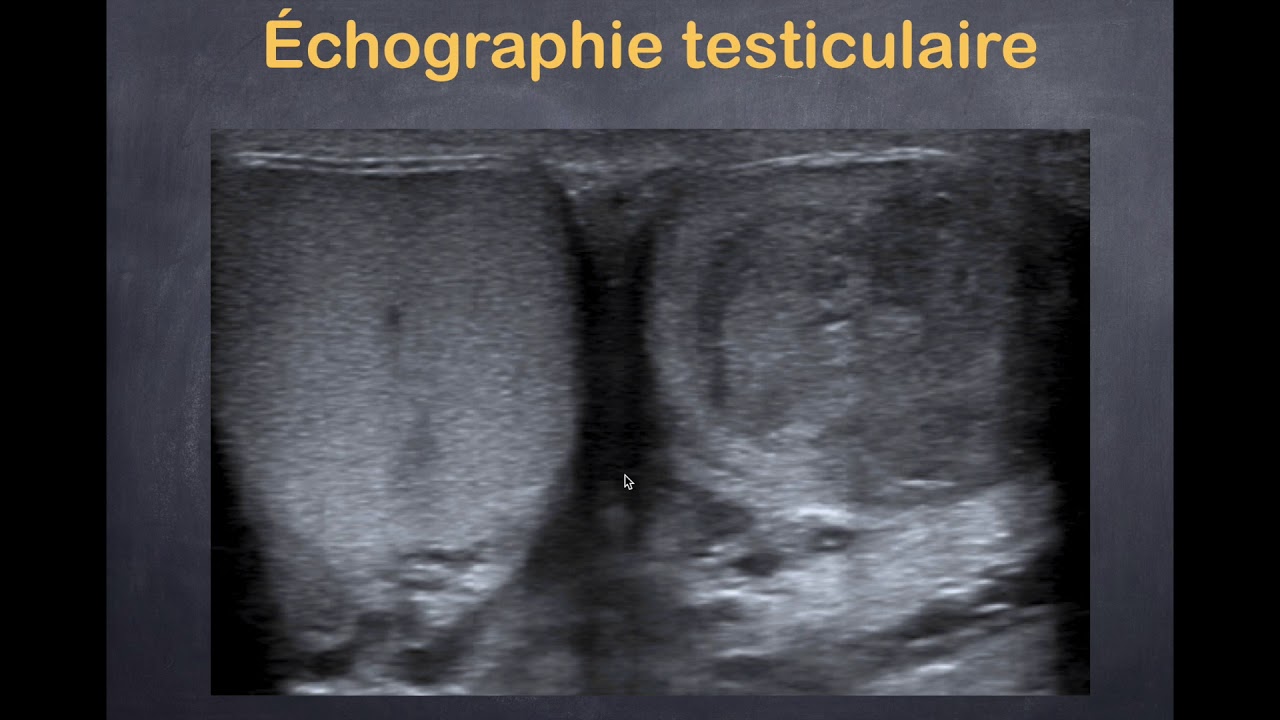

Tumeurs du testicule - 2. Imagerie pathologique